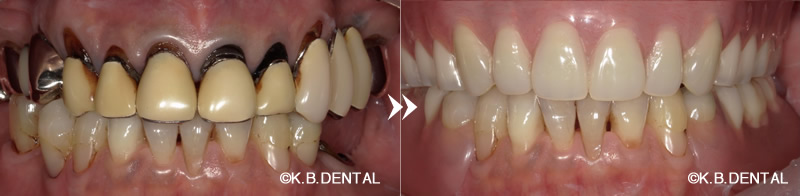

当院での有床金属床義歯症例

口元:術前術後

正面:術前術後

主訴 入れ歯を新調したい。良く噛めるようにしたい。

年齢/性別 50代男性

治療期間 3ヶ月

費用 80万円(税別)

現在の入れ歯が合わないとお悩みの方は、虫歯や歯周病など、何等かのお口の環境が変わる要因による咬み合わせが変わることにあります。

当院では、虫歯・歯周治療をさせていただき、精密な咬合再建・顎位修正を行い、よく噛める金属床義歯をご提供させていただきます。